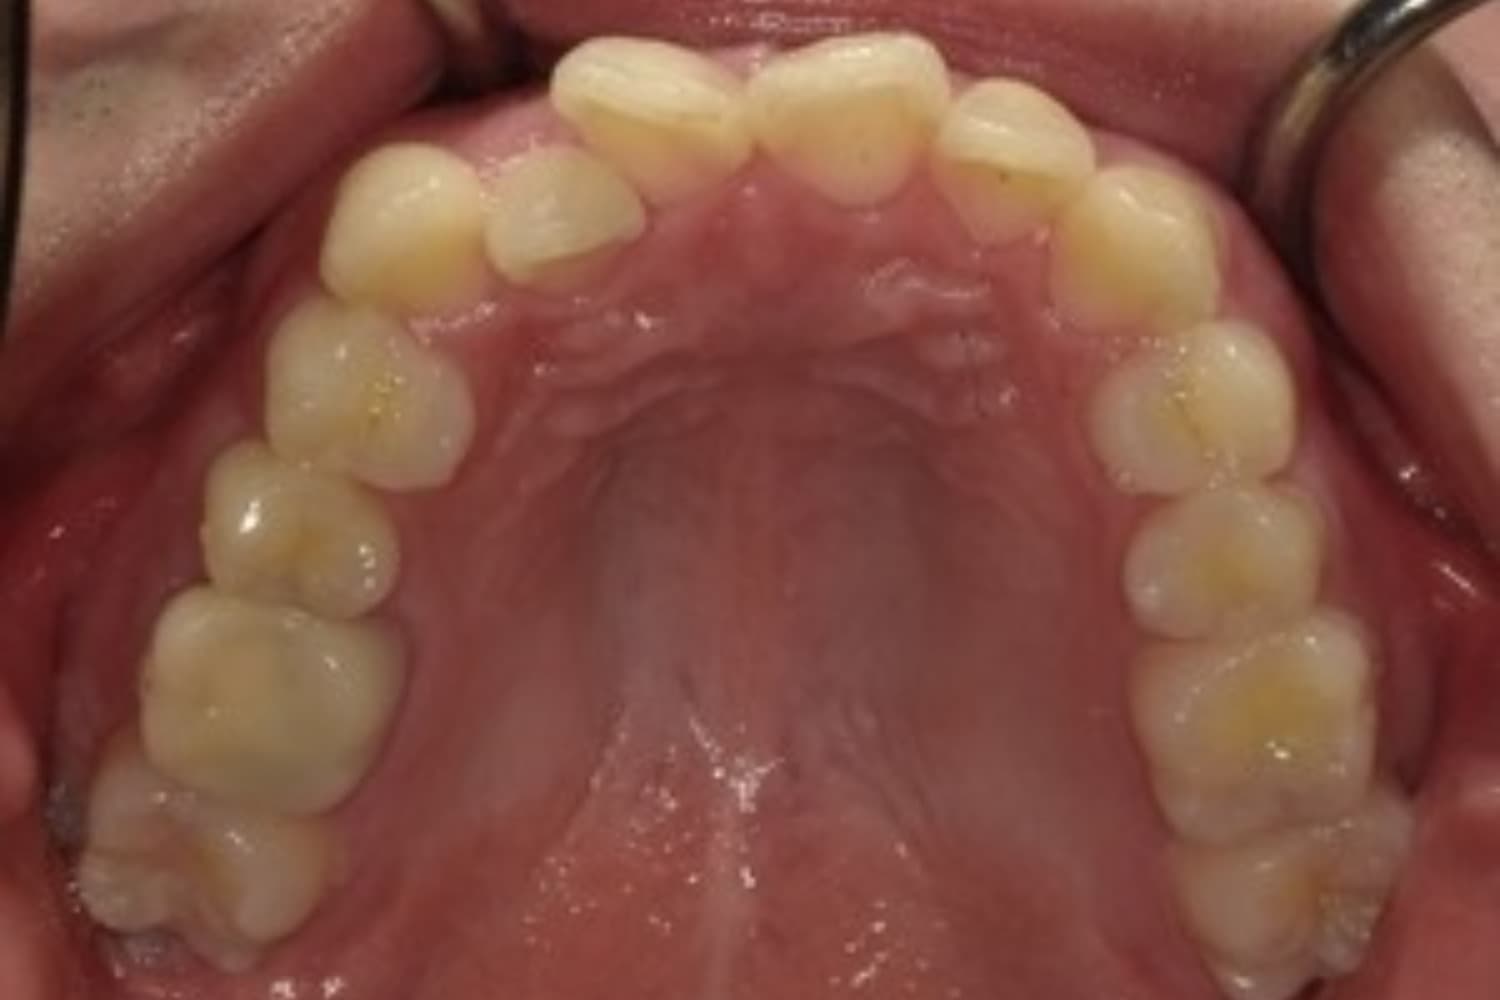

ガタガタとした歯並びや八重歯(1)

Before

After

ガタガタとした歯並びや八重歯をマウスピース矯正(インビザライン)にて治療

主訴

下の前歯のガタガタが気になる

治療期間

2年5カ月

費用

90万円

副作用・リスク

・矯正治療による歯の動きには個人差があり、想定より治療期間が延びることがあります。 ・矯正治療で歯を動かす際に痛みをともなうことがあります。 ・指示された通りに保定装置を装着しないと、歯並びや噛み合わせの後戻りを引き起こす可能性があります。